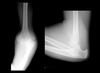

What type of elbow dislocation is this?

Posterior dislocation